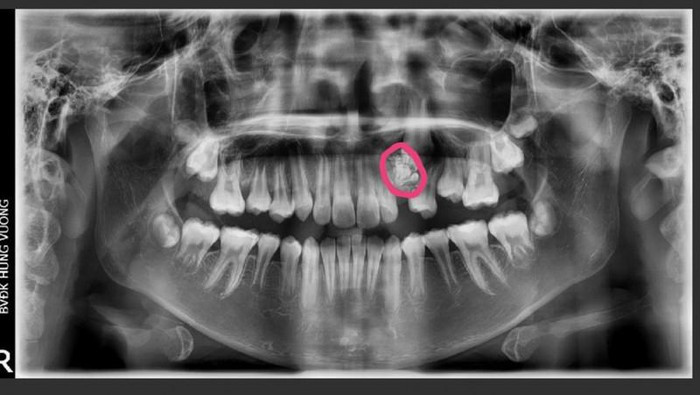

Cách đây 6 tháng bệnh nhân đau ngực, khó thở. Vì dịch Covid-19 nên gia đình chần chừ không đưa bệnh nhân đi bệnh viện. Sau khi tình trạng đau ngực và khó thở tăng, bệnh nhân đi khám phát hiện khối u trong lồng ngực.

Bệnh nhân được điều trị tại Bệnh viện Ung bướu Đà Nẵng 6 đợt hóa chất nhưng thể tích khối u không giảm nên đã chuyển đến Bệnh viện Đà Nẵng để điều trị phẫu thuật.

Bác sĩ chuyên khoa 2 Thân Trọng Vũ - Trưởng khoa Ngoại lồng ngực, Bệnh viện Đà Nẵng - cho biết, đây là trường hợp phức tạp, gây khó khăn bởi khối u có kích thước lớn, nằm chiếm gần hết khoang lồng ngực, chèn ép tim và gây xẹp hoàn toàn phổi trái. Vì vậy, ê kíp phẫu thuật phải làm sao để đảm bảo lấy trọn khối u mà không gây vỡ u, đảm bảo an toàn tránh các biến chứng.

"Theo y văn thế giới, các khối u trung thất kích thước lớn như của bệnh nhân H. là trường hợp rất hiếm gặp", bác sĩ Vũ cho biết thêm.